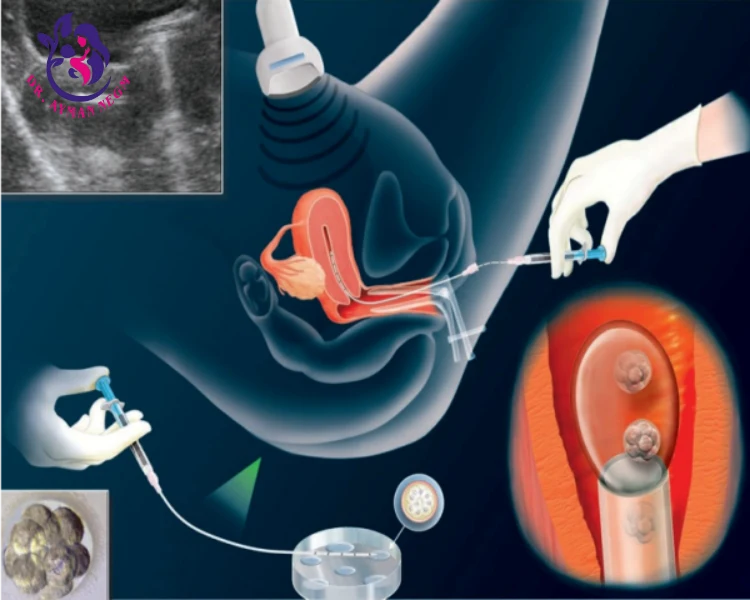

الحقن المجهري (ICSI) هو نوع من تقنيات المساعدة على الإنجاب، حيث يتم فيه حقن حيوان منوي واحد مباشرة داخل البويضة باستخدام إبرة دقيقة تحت المجهر. يتم اللجوء إلى هذه التقنية في حالات معينة مثل:

يتم إجراء هذه العملية في مختبر متخصص ضمن خطوات معينة تبدأ بتحفيز الإباضة في المرأة باستخدام أدوية هرمونية، ثم يتم جمع البويضات من المبيض، وبعدها يتم حقن الحيوان المنوي في البويضة باستخدام إبرة دقيقة. بعد نجاح الإخصاب، يتم زرع البويضة المخصبة في رحم المرأة.

الحقن المجهري-التلقيح المجهري هو متخصص شكل الإخصاب في الأنابيب التي تستخدم في الغالب عادة في الحالات الشديدة العقم عند الذكور ، بعد تكرار فشل محاولات الإخصاب مع التلقيح الاصطناعي التقليدية ، أو بعد تجميد البويضات (البويضة المحافظة).(1) تنطق ick-see IVF ، ICSI تعني حقن الحيوانات المنوية داخل الأورام النباتية. يتم وضع العديد من الحيوانات المنوية مع البويضة ، أثناء التلقيح الصناعي العادي ، على أمل أن يدخل أحد الحيوانات المنوية ويخصب البويضة من تلقاء نفسه. مع ICSI-IVF ، يأخذ عالم الأجنة حيمن واحد ويحقنه مباشرة في بيضة.1